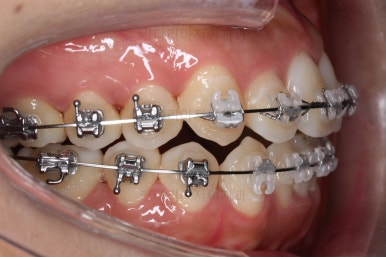

초진 시 입안의 모습입니다.

그냥 봐도 뭔가 애매함이 있죠?

중앙선이 맞지 않고, 교합이 떠보이는 양상이네요.

윗니는 좌측 작은 어금니가 한 개 모자랐고 아랫니는 앞니 하나가 모자라네요.

그런데 앞니는 아랫니가 1개 모자란 채로 교합이 맞춰져서 윗니가 하나 부족한 채로 애매한 상태였어요.